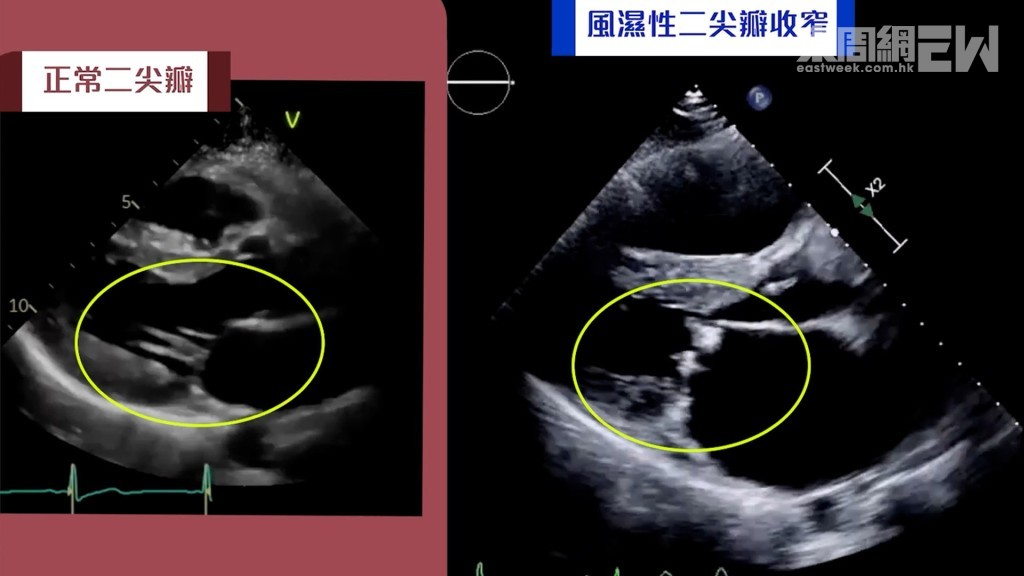

如醫生懷疑病人有心瓣膜病,一般會建議病人進行心臟超聲波檢查,作為診斷的最重要一環,以獲取心瓣結構及功能的詳細資訊幫助診斷。心臟超聲波,是非入侵性和沒有傷害性的檢查,透過超聲波可以深入觀察心臟大小結構及收縮放鬆功能、各個心瓣的運作情況,以至掌握心瓣膜病的成因。

心瓣膜病的成因有很多,最常見的是退化性心瓣膜病,通常與年齡有關。患者隨年齡增長,心瓣自然老化及退化,如出現鈣化現象導致心瓣收窄打不開令血液無法前行,又或出現鬆弛導致心瓣關不上引致血液倒流。其他成因包括風濕性心瓣膜病,這種情況通常源於兒童或青少年時期的細菌感染,導致免疫系統攻擊心瓣組織,患者可能早於四、五十歲便發病。

風濕性心瓣膜病通常源於兒童或青少年時期的細菌感染,患者可能年屆四、五十歲便發病。圖為正常二尖瓣與風濕性二尖瓣收窄的超聲波影像。

如醫生懷疑病人有心瓣膜病,一般會建議病人進行心臟超聲波檢查,作為診斷的最重要一環,以獲取心瓣結構及功能的詳細資訊幫助診斷。